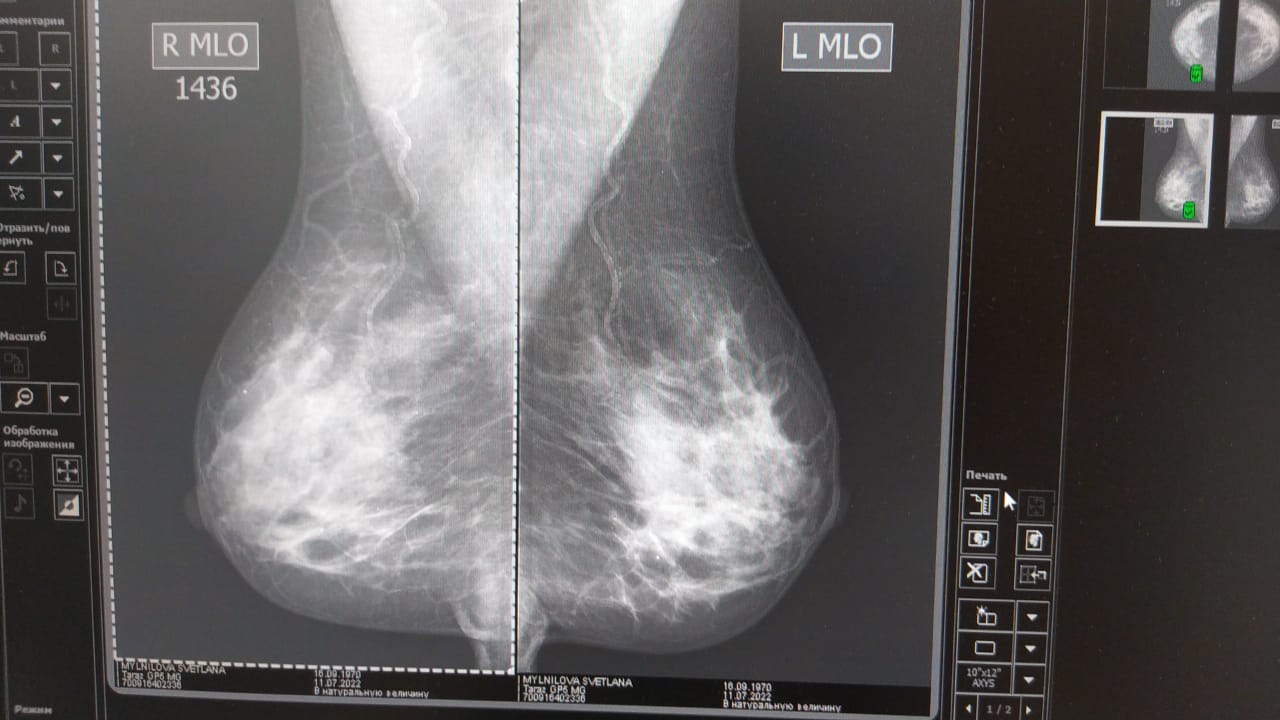

Что такое маммография? Маммография - это распространенный, точный и наиболее эффективный способ обследования здоровья груди на сегодняшний день. Достоверность результатов обследования молочных желез зависит как от качественного и сертифицированного оборудования, так и от квалификации врача, который делает оценку результатов. Скрининговую маммограмму, при наличии показаний, важно делать ежегодно, она позволяет выявить раковые заболевания наиболее ранних и излечимых стадиях заболевания. К примеру, именно маммография позволяет увидеть аномальное развитие ткани за два года до того, как врач или вы, сможете выявить такие изменения пальпацией (руками). Именно рентгеновский скрининг показан для пациенток из так называемой группы риска: женщины после 45 лет женщины любого возраста, у которых есть подозрение на опухолевые новообразования, обнаруженные во время мануального осмотра или УЗИ исследования; женщины любого возраста, у которых ближайшие прямые родственницы имели/имеют рак молочной железы. Обследование заключается в рентгеновских снимках (отдельно отличают 3D-цифровую маммографию и УЗИ молочных желез), которые фиксируют изображение ткани молочных желез в различных проекциях. Врач рентгенолог интерпретирует изображения и сообщает результаты пациенту. Проводя плановое ежегодное обследование и пользуясь тем самым мамографом, рентгенолог имеет дополнительное преимущество в сравнении текущего результата обследования с предыдущим, что помогает и облегчает выявление крошечных отклонений, которые могут появиться от года в год. Что покажет маммограма? Обзорная маммография дает следующие результаты: отсутствие признаков раковых заболеваний тканей; опухолевые образования не злокачественного происхождения; аномальные изменения тканей, которые требуют дополнительного обследования на предмет подтверждения ракового заболевания. Чем отличаются скрининговая и диагностическая маммографии? Скрининговая маммография является обзорным методом обследования, которое позволяет оценить состояние тканей и наличие в них аномальных изменений опухолевого характера. Диагностическая маммография является прицельным изучением обнаруженных аномальных изменений в тканях для постановки точного диагноза и выбора лечебных мероприятий. Является ли маммография болезненной? Как правило, маммография не вызывает болевых ощущений, но некоторые женщины сообщают о дискомфорте во время процедуры. Собственно обследование проводится с зажиманием молочной железы между двумя пластинами-платформами для снимка. Если сжатие слишком неприятно и вызывает боль, можно попросить рентгенолога изменить положение груди, чтобы облегчить дискомфорт. На объем дискомфорта или боли влияют размер груди, день менструального цикла, опытность рентгенолога. Для большинства женщин лучшее время для безболезненного проведения обследования подходит любой день в течение первой недели после окончания менструального цикла. Если возможно, не планируйте скрининг груди на неделе до начала менструального цикла, поскольку именно тогда грудь наиболее чувствительна к боли.